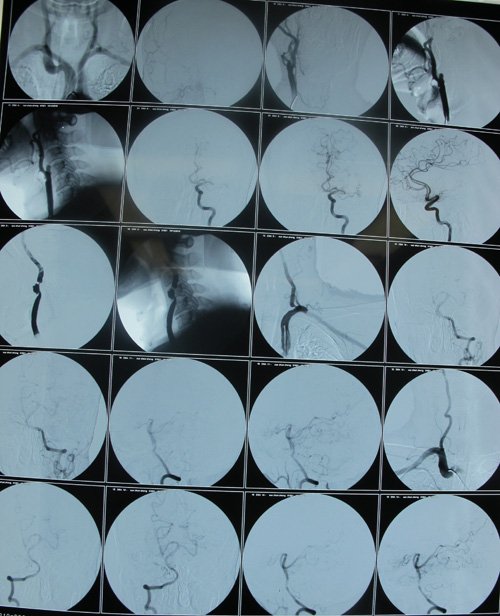

头颈CTA示:右侧颈内动脉近端闭塞,左侧颈总动脉远端及颈内动脉近端重度狭窄

颈部血管超声示:双侧颈动脉粥样斑块形成伴左侧颈动脉狭窄(重度)。

该患者为急性起病,既往脑梗塞病史13年,心肌梗塞病史1年。右侧颈内动脉近端闭塞,左侧颈总动脉远端及颈内动脉近端重度狭窄,均达到手术指征。患者无明确手术禁忌症,故采取手术治疗,去除病变,改善症状并预防中风发作。

2010年12月25日,协作组张勤奕教授前往同煤集团总医院,顺利为该患者实施了左侧颈动脉内膜剥脱术,定于3个月到半年后再考虑右侧手术。